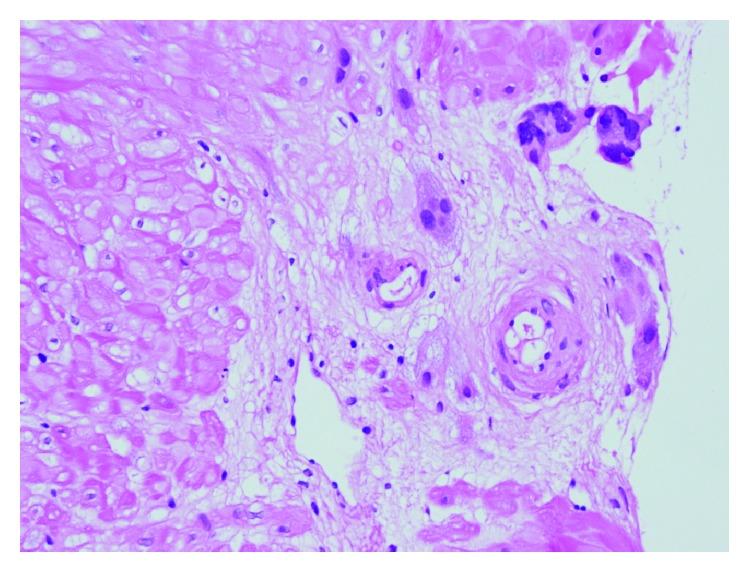

孕早期与孕中期子宫动脉多普勒测速与胎盘床组织病理学之间的相关性

Correlation between First and Second Trimester Uterine Artery Doppler Velocimetry and Placental Bed Histopathology.

Aim. To evaluate the relationship between uterine artery Doppler indices and placental bed histopathology independent of clinical outcome. Materials and Methods. Uterine artery measurements were performed to 510 pregnant women who had come for routine antenatal care in 11-14th and 20-24th weeks. Placental bed biopsies from 141 cases were taken during cesarean section. Physiological changes and abnormal placental histology findings were investigated and compared with Doppler findings. Results. 116 biopsies were accepted as adequate biopsy and included in the study. Physiological changes were seen in 100 biopsies. Statistically significant higher PI and RI values in second trimester and higher notch rate in both trimesters were detected in the abnormal placental histology group (P < 0,001). Conclusion. Strong relationship between uterine artery Doppler indices and preeclampsia or intrauterine growth retardation has been shown in previous studies. In our study, we concluded that there is significant relationship between Doppler findings and placental bed histopathology independent of clinical course.

目的。评估子宫动脉多普勒指数与胎盘床组织病理学之间的关系,而不考虑临床结局。材料与方法。对510名在孕11 - 14周和20 - 24周前来进行常规产前检查的孕妇进行子宫动脉测量。在剖宫产时从141例病例中获取胎盘床活检组织。研究生理变化和异常胎盘组织学发现,并与多普勒检查结果进行比较。结果。116份活检组织被认为是足够的活检样本并纳入研究。100份活检组织出现生理变化。在异常胎盘组织学组中,检测到孕中期的搏动指数(PI)和阻力指数(RI)值在统计学上显著更高,且两个孕期的切迹率均更高(P < 0.001)。结论。先前的研究表明子宫动脉多普勒指数与子痫前期或胎儿生长受限之间存在密切关系。在我们的研究中,我们得出结论,多普勒检查结果与胎盘床组织病理学之间存在显著关系,且与临床过程无关。